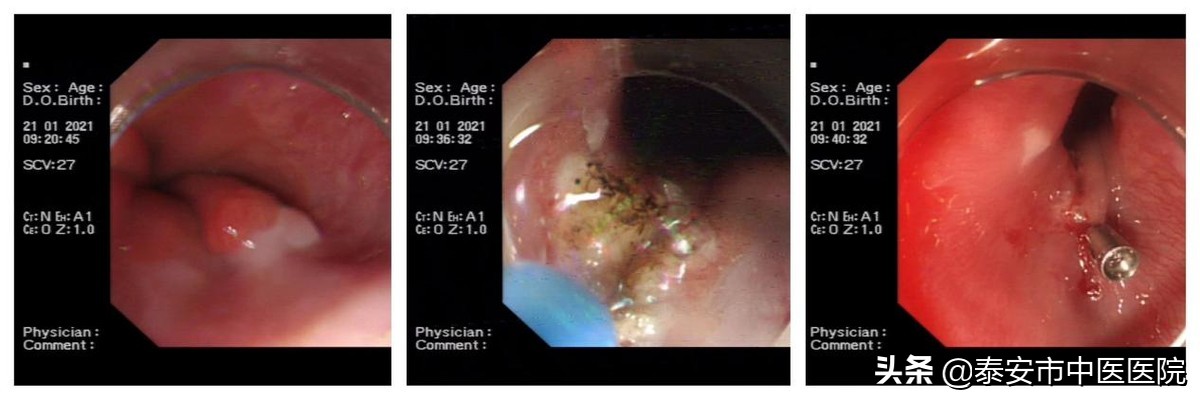

近日,81岁的李大爷因上腹部不适到*安泰**市中医医院就诊,行胃镜检查,脾胃病科主任张伟使用高清放大胃镜发现患者贲门附近小片状充血病灶,精准活检后病理报告显示为粘膜内高分化腺癌。如下图:

1.危险区(贲门息肉EMR),照样切除: